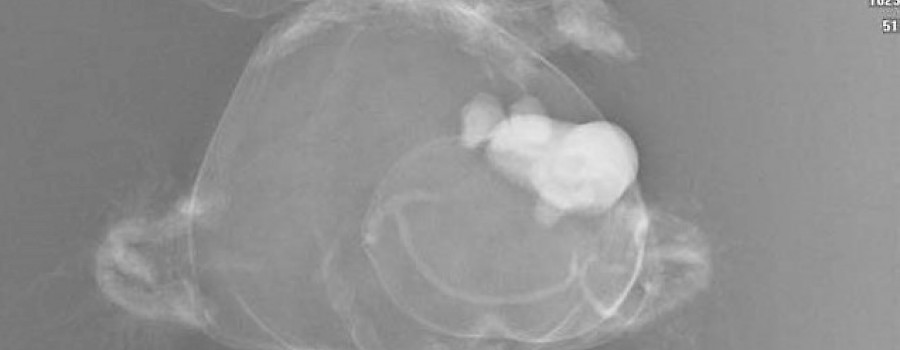

Wir einigten uns, dass auch Minihops Schmerzen habe, und so schlug ich ihr vor, doch zuerst mal ihren treuen Begleiter zu röntgen, damit sie sieht, dass da gar nichts schlimmes passiert. Nach etwas zögern rückte sie Minihops heraus und ich legte ihn immer noch unter skeptischer und ängstlicher Beobachtung des Mädchens auf eine Kassette unter die Röntgenröhre.

Dem Mädchen erklärte ich jeden Schritt den ich tat und ging mit ihr – immer noch an der Mutter klebend - zum Schaltpult, löste den Schuss aus, ging zum Auslesegerät und ließ die Kleine zuswehen, wie das Bild aufgebaut wurde. So langsam merkte ich wie sie langsam auftaute. Jedenfalls ließ das Geschluchze erheblich nach und der Klammergriff zur Mutter löste sich auch schon merklich. Wir besprachen das Bild von Minihops und stellten fest, dass das Kuscheltier keinerlei Brüche oder sonstige ernsthafte Erkrankungen habe!

Das Bild von Minihops habe ich ihr später an die eMail-Adresse der Mutter nach Hause geschickt!